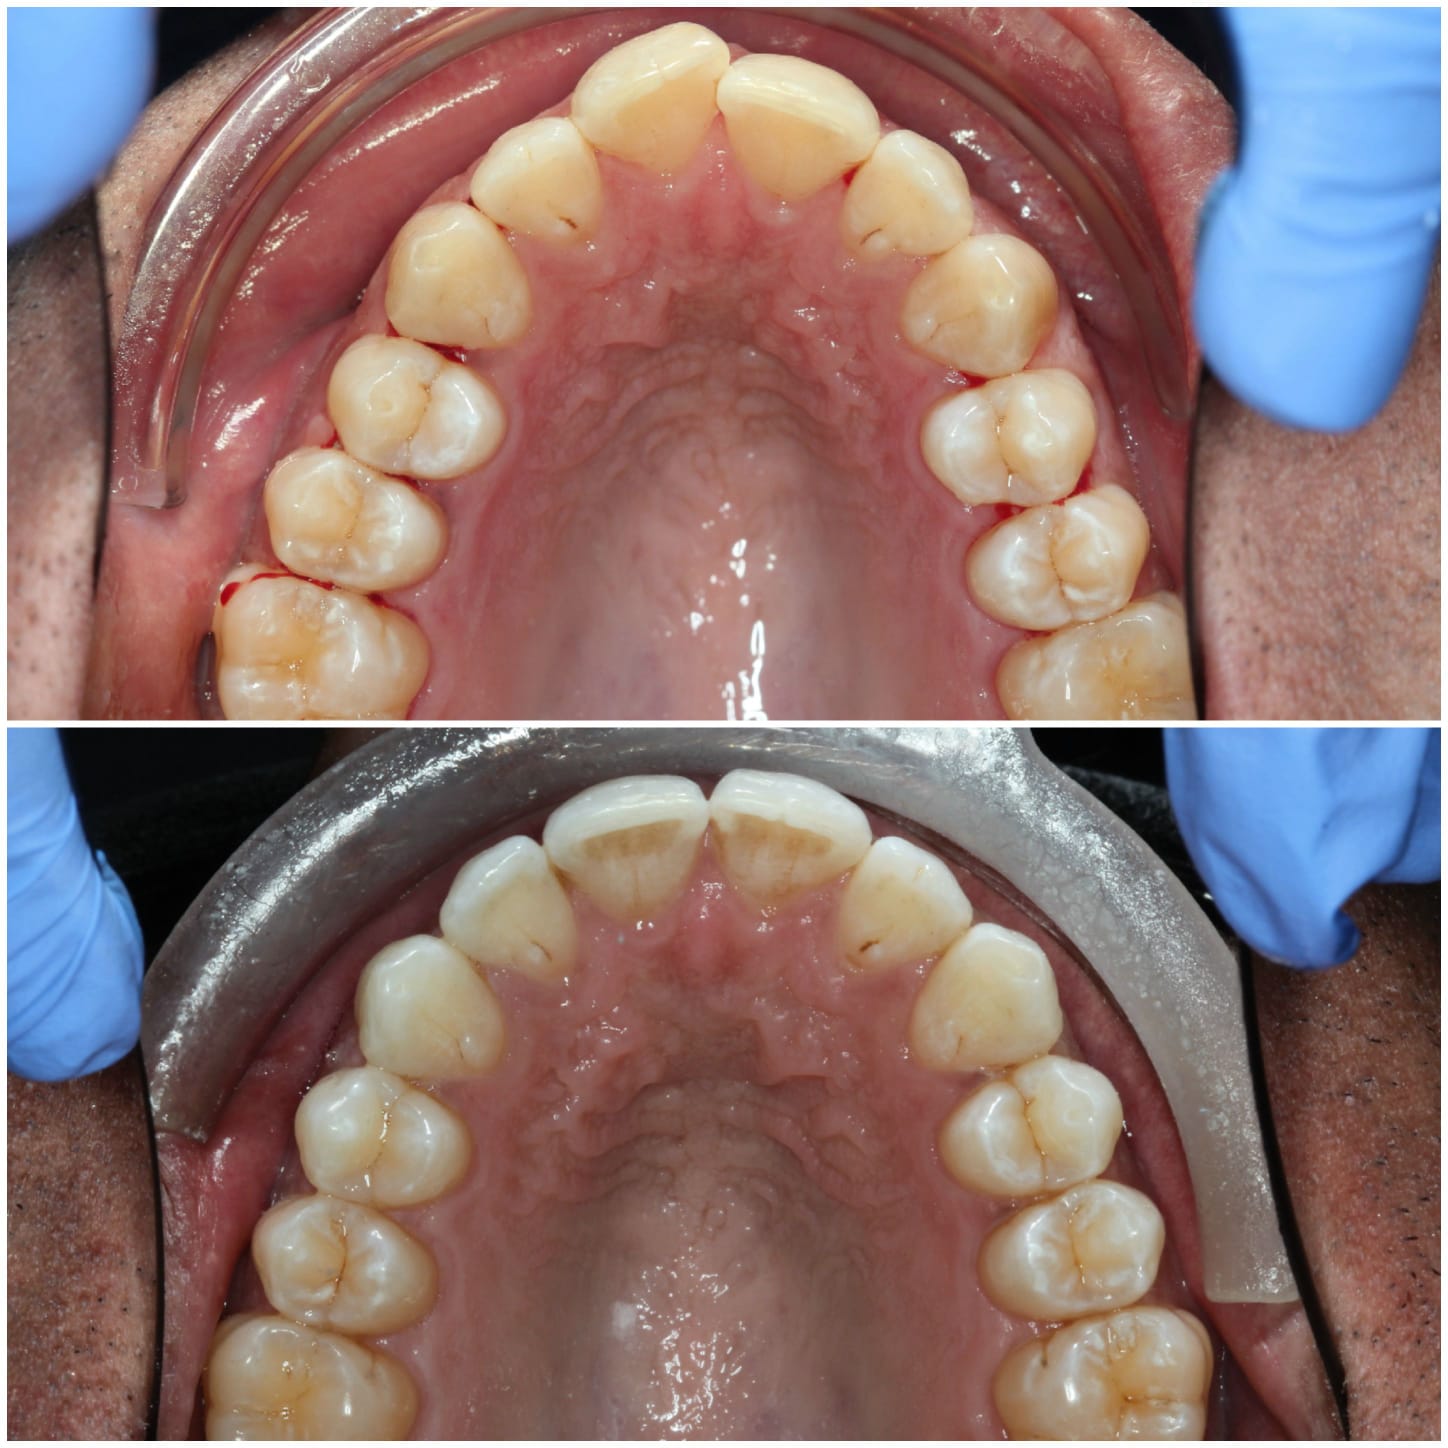

Invisalign is a well-known system for straightening teeth in the most discreet way. It works by using a series of clear aligners that fit comfortably over the teeth to gently move them into the desired position over time. There are no fixed brackets or wires used, in fact, the aligners are completely removable.

Virtually invisible way to straighten your teeth

Removable aligners make eating and dental care easy